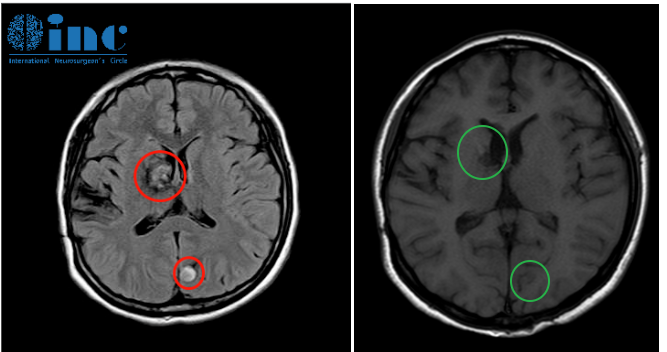

16年过去了,当佳佳父母找到INC巴教授。一次住院3周时间,巴教授通过高精度神经电生理监测,分两次手术全切基底节和顶枕叶病变,术后无并发症。

术前术后影像对比(红色术前,绿色术后)